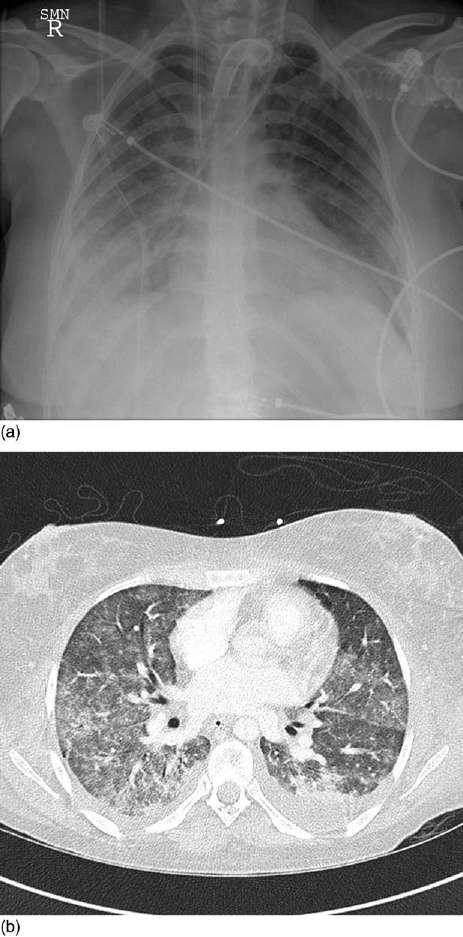

ChestCTdemonstratesthatthelungsareaffected inaheterogenousmanner.Typically,thereisagradientofopacificationfromapparentlynormally aeratedlung,throughground-glassappearances,to denselyconsolidatedlung.Inthesupinepatient,this gradientoccursbothinventrodorsalandcephalocaudaldirections.Thesegradientstypicallyreverse withinafewminutesifthepatientismovedtothe proneposition.Sincealveolaredemawouldnotredistributesoquickly,someoftheseappearanceare notduetoincreasededemaindependentzonesbut duetocollapseoftheseareasduetotheweightofthe overlyinglung.Thusground-glassappearancesmost likelyrepresentairspaceedema,withdenselyopacifiedareasrepresentingcollapsededematouslung. Regionsofdenseopacificationinnondependentareasmaysignifycollapse/consolidationduetoinfectionorretainedsecretions.Atlaterstages,groundglassappearancesmaybeaccompaniedbybronchial dilatationwhichpersistsintorecovery,suggesting establishedfineintralobularfibrosis(Figure1).

Figure1 TypicalappearancesofARDSwith(a)plainradiology and(b)computedtomography.